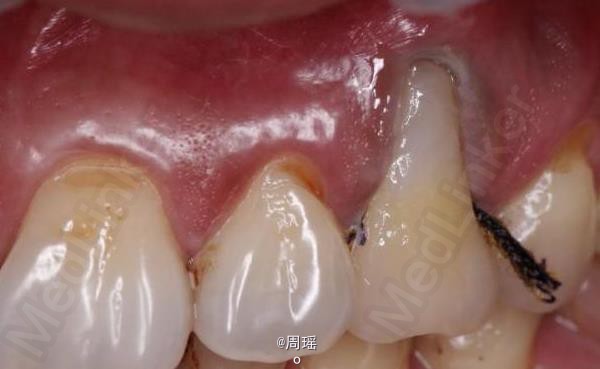

楔状缺损的充填

楔状缺损

患者,男,40岁,左上第一前磨牙楔状缺损来诊。平素体质一般,无系统性疾病和高血压、心脏病等病史,无药物、食物过敏史。